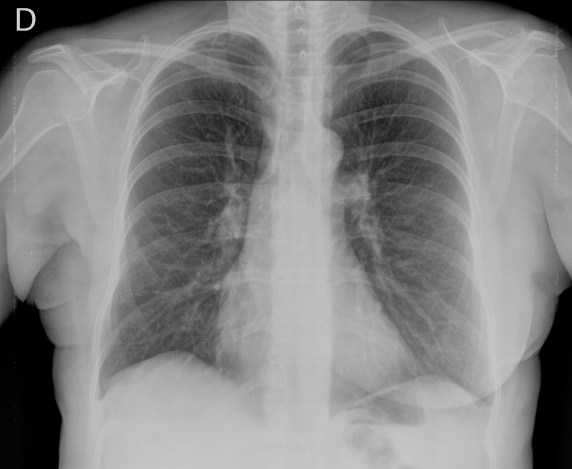

Mismo paciente, al cual esta vez se le ha tomado una radiografía en PA y en sedestación. Observar como las clavículas están equidistantes a las apófisis espinosas y como ha desaparecido el velamiento del pulmón izquierdo.

Por otra parte, paciente presenta una cardiomegalia y un discreto ensanchamiento del mediastino es probable relación con cambios postquirúrgicos.